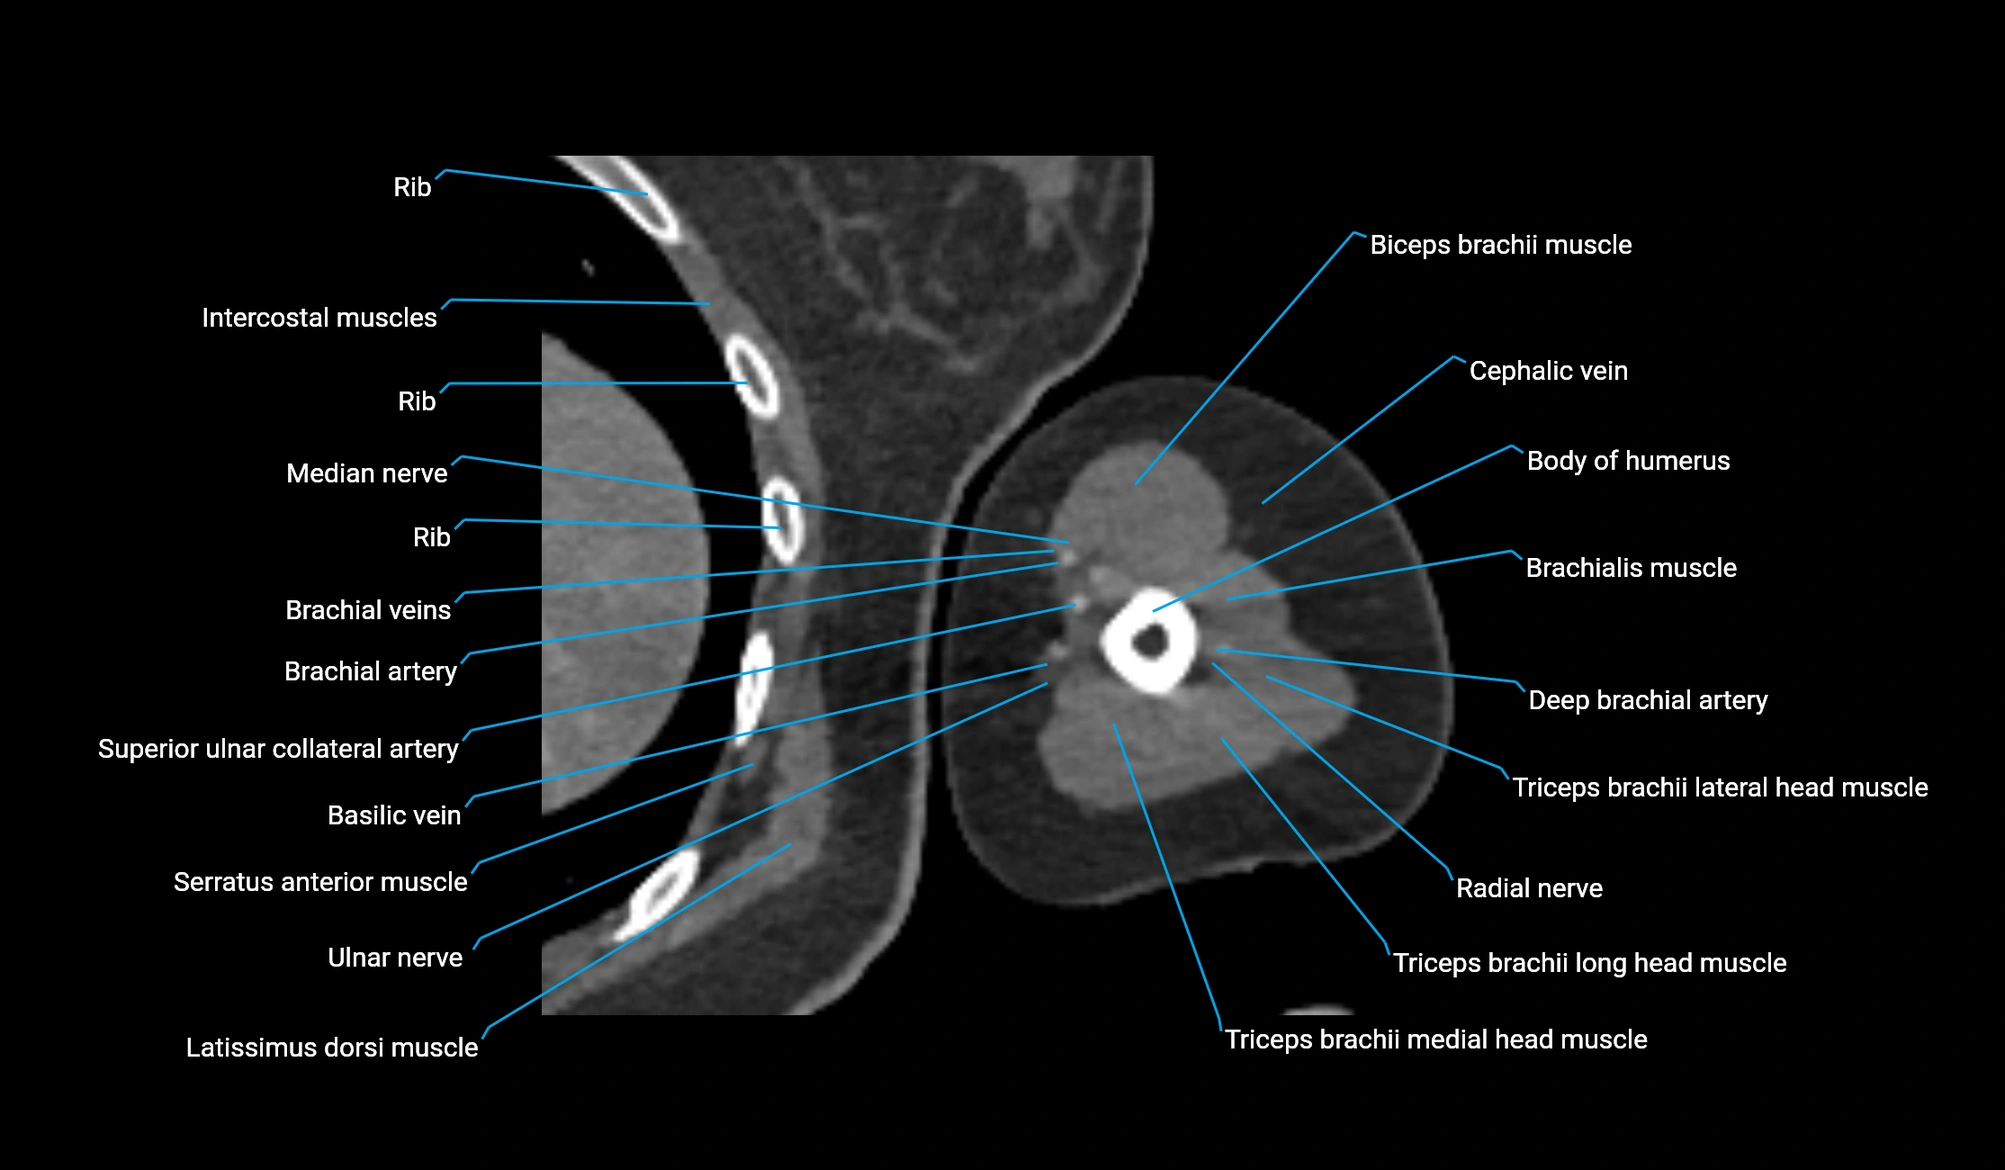

- Biceps brachii muscle

- Body of humerus

- Brachial artery

- Brachialis muscle

- Cephalic vein

- Deep brachial artery

- Long head of triceps brachii muscle

- Medial head of triceps brachii muscle

- Median nerve

- Radial nerve

- Superior ulnar collateral artery

- Ulnar nerve